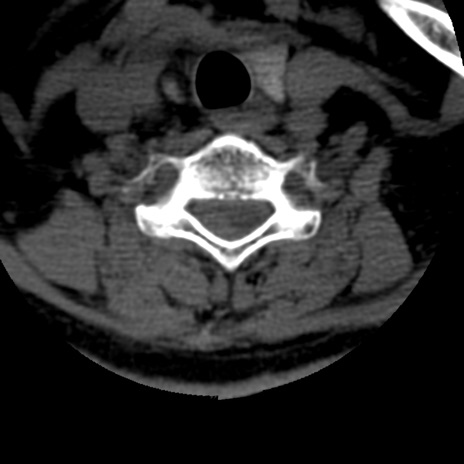

症例50 頚椎CT(横断像)

異常所見と診断は?

冠状断像